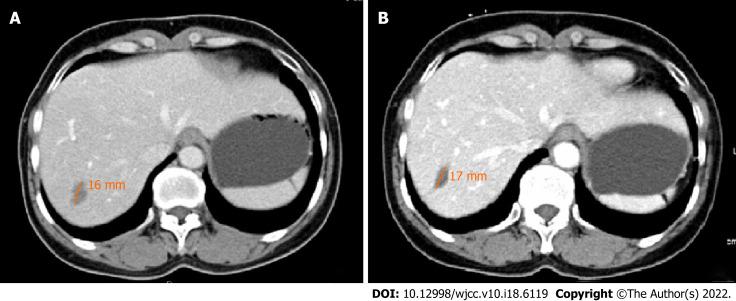

A 46-year-old woman with abdominal discomfort and elevated serum carcinoembryonic antigen was found to have multiple low-density lesions in the liver and lung on computed tomography (CT) evaluation. An ultrasound-guided fine needle aspiration biopsy revealed a fibrous stroma with dendritic cells, containing intracellular vacuoles. Immunohistochemical staining found that the tumor cells were positive for CD34, CD31, and factor VIII-related antigen. The patient received four courses of combined chemotherapy and was followed-up for 13 years, at which time the patient was in stable condition without disease progression and a confined neoplasm, as evidenced by CT scans.

一名 46 岁女性,有腹部不适且血清癌胚抗原升高,计算机断层扫描(CT)评估发现肝脏和肺部有多个低密度病变。超声引导下细针穿刺活检显示有含树突状细胞的纤维性基质,细胞内有液泡。免疫组织化学染色发现肿瘤细胞对 CD34、CD31 和因子 VIII 相关抗原呈阳性。该患者接受了四个疗程的联合化疗,并随访 13 年,此时患者病情稳定,无疾病进展且肿瘤局限,CT 扫描证实了这一点。